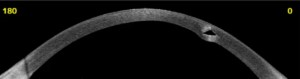

Het aanmeten van keratoconuslenzen vraagt om precisie en ervaring. Bij JGK wordt de exacte hoornvliestopografie in kaart gebracht met een corneatopograaf en een OCT-scan (optische coherentietomografie), die de dikte en het verloop van het hoornvlies nauwkeurig vastlegt. Op basis hiervan selecteert onze specialist het meest passende lensdesign.

Een nauwkeurige meting is de basis van een goede keratoconuslens. Bij JGK wordt gebruik gemaakt van een corneatopograaf (Medmont) voor het in kaart brengen van de hoornvlisvorm, een Eaglet Eye Surface Profiler (ESP) met meer dan 250.000 meetpunten voor de exacte oogvorm inclusief sclera, en een OCT voorsegmentscan voor gedetailleerde dikte- en vormanalyse van de cornea. Met de ESP is het aanmaken van een oogafdruk in vrijwel alle gevallen overbodig geworden.

Scleralenzen zijn grote harde contactlenzen met een diameter van 14 tot 25 mm die volledig over het hoornvlies heen vallen en rusten op het oogwit (sclera). Doordat ze het hoornvlies niet raken, zijn ze uitermate geschikt bij alle vormen van keratoconus, keratoglobus, pellucid marginal degeneration, na een hoornvliestransplantatie en na laserbehandelingen. JGK beschikt over de meest geavanceerde apparatuur voor individuele aanpassing van scleralenzen en werkt samen met vrijwel alle Europese lensfabrikanten voor maatwerk.